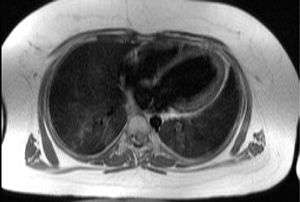

Transaxial image of the chest at the level of the heart illustrating the typical degree of subcutaneous and epicardial adipose tissue (shown in white) in a patient with Alström syndrome; hence the difficulty in imaging by echocardiography. | |